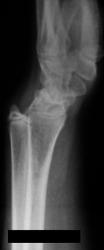

Девочка 14 лет. Ранее за помощью не обращались. Только в этом возрасте родителей и саму пациентку начала беспокоить деформация предплечий.

Рентгенологическая классика для болезни Маделунга:

1. Укорочение лучевой кости.

2. «Скошенность» суставной поверхности дистального эпифиза лучевой кости в ладонную и локтевую сторону, что «симулирует» визуально подвывих костей запястья.

3. «Нависание» полулунной кости над ладонным краем дистального эпифиза лучевой кости.

4. Высота дистального эпифиза по лучевой стороне превосходит его высоту по локтевой стороне.

5. В результате раннего закрытия ростковой зоны по локтевой и ладонной стороне, формируется ладонный и локтевой наклон суставной поверхности.

6. Деформация и изменение расположения проксимального ряда костей запястья, по форме, напоминающей «клин», вершиной которого является полулунная кость.

7. Головка локтевой кости находится в положении «вывиха» и смещена в «тыльном» направлении, по отношению к лучезапястному суставу.